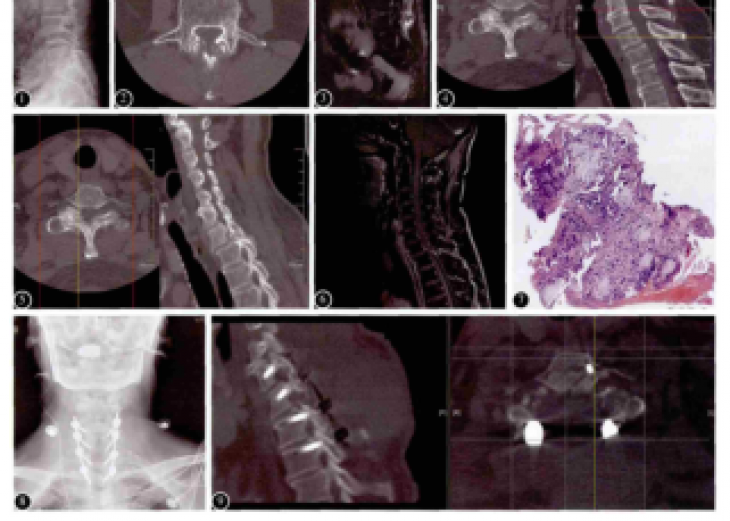

Maisonneuve损伤因涉及下胫腓联合韧带的损伤及腓骨近端骨折,易造成踝关节对合关系及稳定性改变,往往需要手术治疗,手术虽不复杂却存在严重失误的风险。本文通过总结1例Maisonneuve损伤手术治...